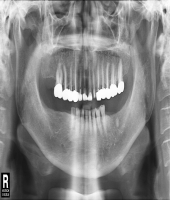

| ● 진료과목 : [임플란트] 치주환자의 임플란트 보철치료

| ● 내용 : 50대 치주환자의 임플란트치료. |